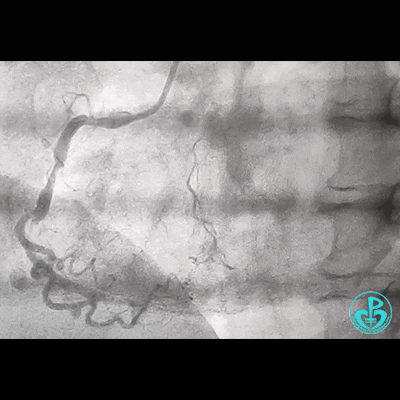

冠脉造影

右锁骨下动脉迂曲打圈,影像如下: